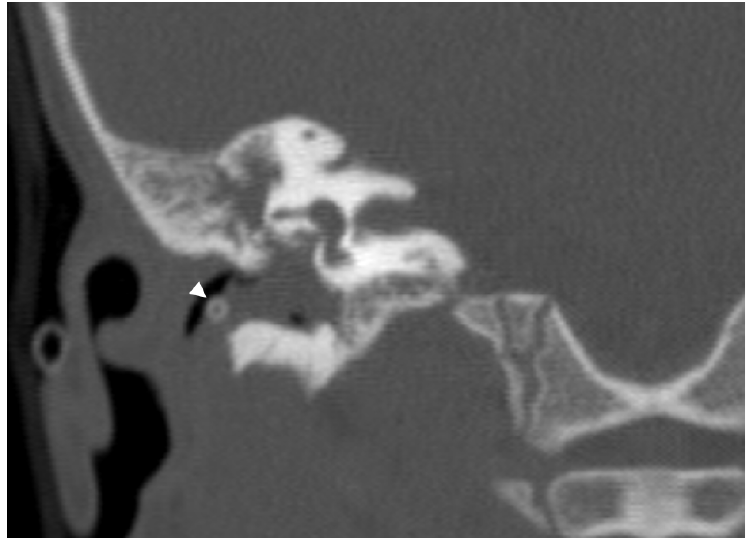

Figure 1 CT-scan of the right ear showing complete obliteration of the middle ear with soft tissue density material that protruded thought the tympanic membrane into the external ear canal displacing the ventilation tube (arrowhead).

A contrasted head CT-scan revealed complete opacification of the right mastoid and middle ear with soft tissue density material that protruded thought the tympanic membrane into the external ear canal displacing the ventilation tube (Figure 1). The ossicular chain was intact and there was no dehiscence of the tegmen tympani or of the tegmen mastoideum. The scutum was intact. The left tympanic membrane was thickened, and the ventilation tube was in the correct position. The ipsilateral middle ear and mastoid were aerated.